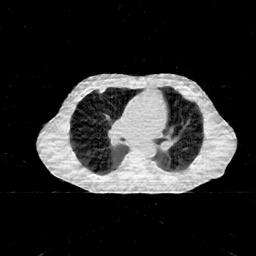

IV-D Limited-Angle CT Reconstruction

To test the proposed framework’s performance on limited-angle reconstruction, we redo the experiment in the above section with the angular range changing from to for parallel-beam geometry and to for fan-beam geometry, one projection per degree. The experiment results are shown in Fig.6. Also, the ground truth and the limited-angle CT reconstruction results of different methods are shown in the row of Fig.7 (parallel-beam, LIDC-IDRI dataset), and Fig.8 (fan-beam, LIDC-IDRI dataset).

(a) Ground Truth

30.15dB/0.85

(b) ASD-POCS

39.35dB/0.94

(c) RBP-DIP

27.10dB/0.78

(d) DIP

23.88dB/0.65

(e) MED50

20.59dB/0.60

(f) RED-CNN